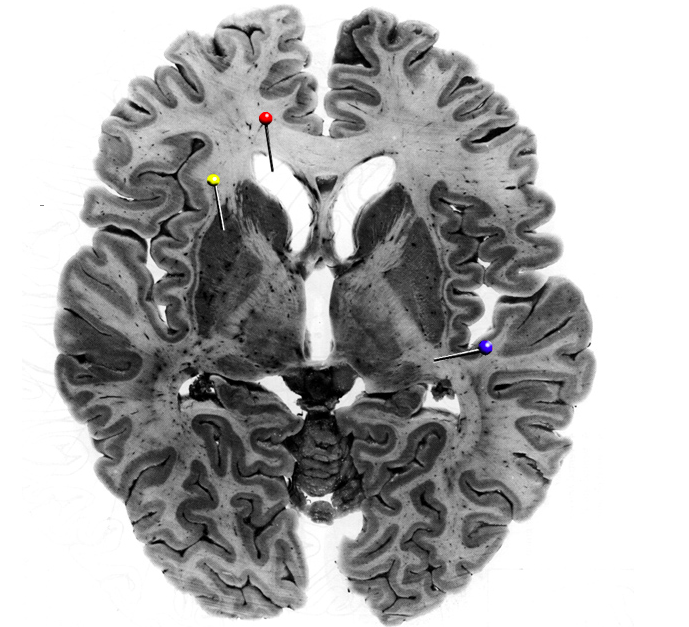

In the horizontal brain slice, the yellow pin is in the…

Putamen

This is a basal nuceleus; initiates voluntary movements and coordinates slow skeletal muscle contractions (e.g., posture and balance)